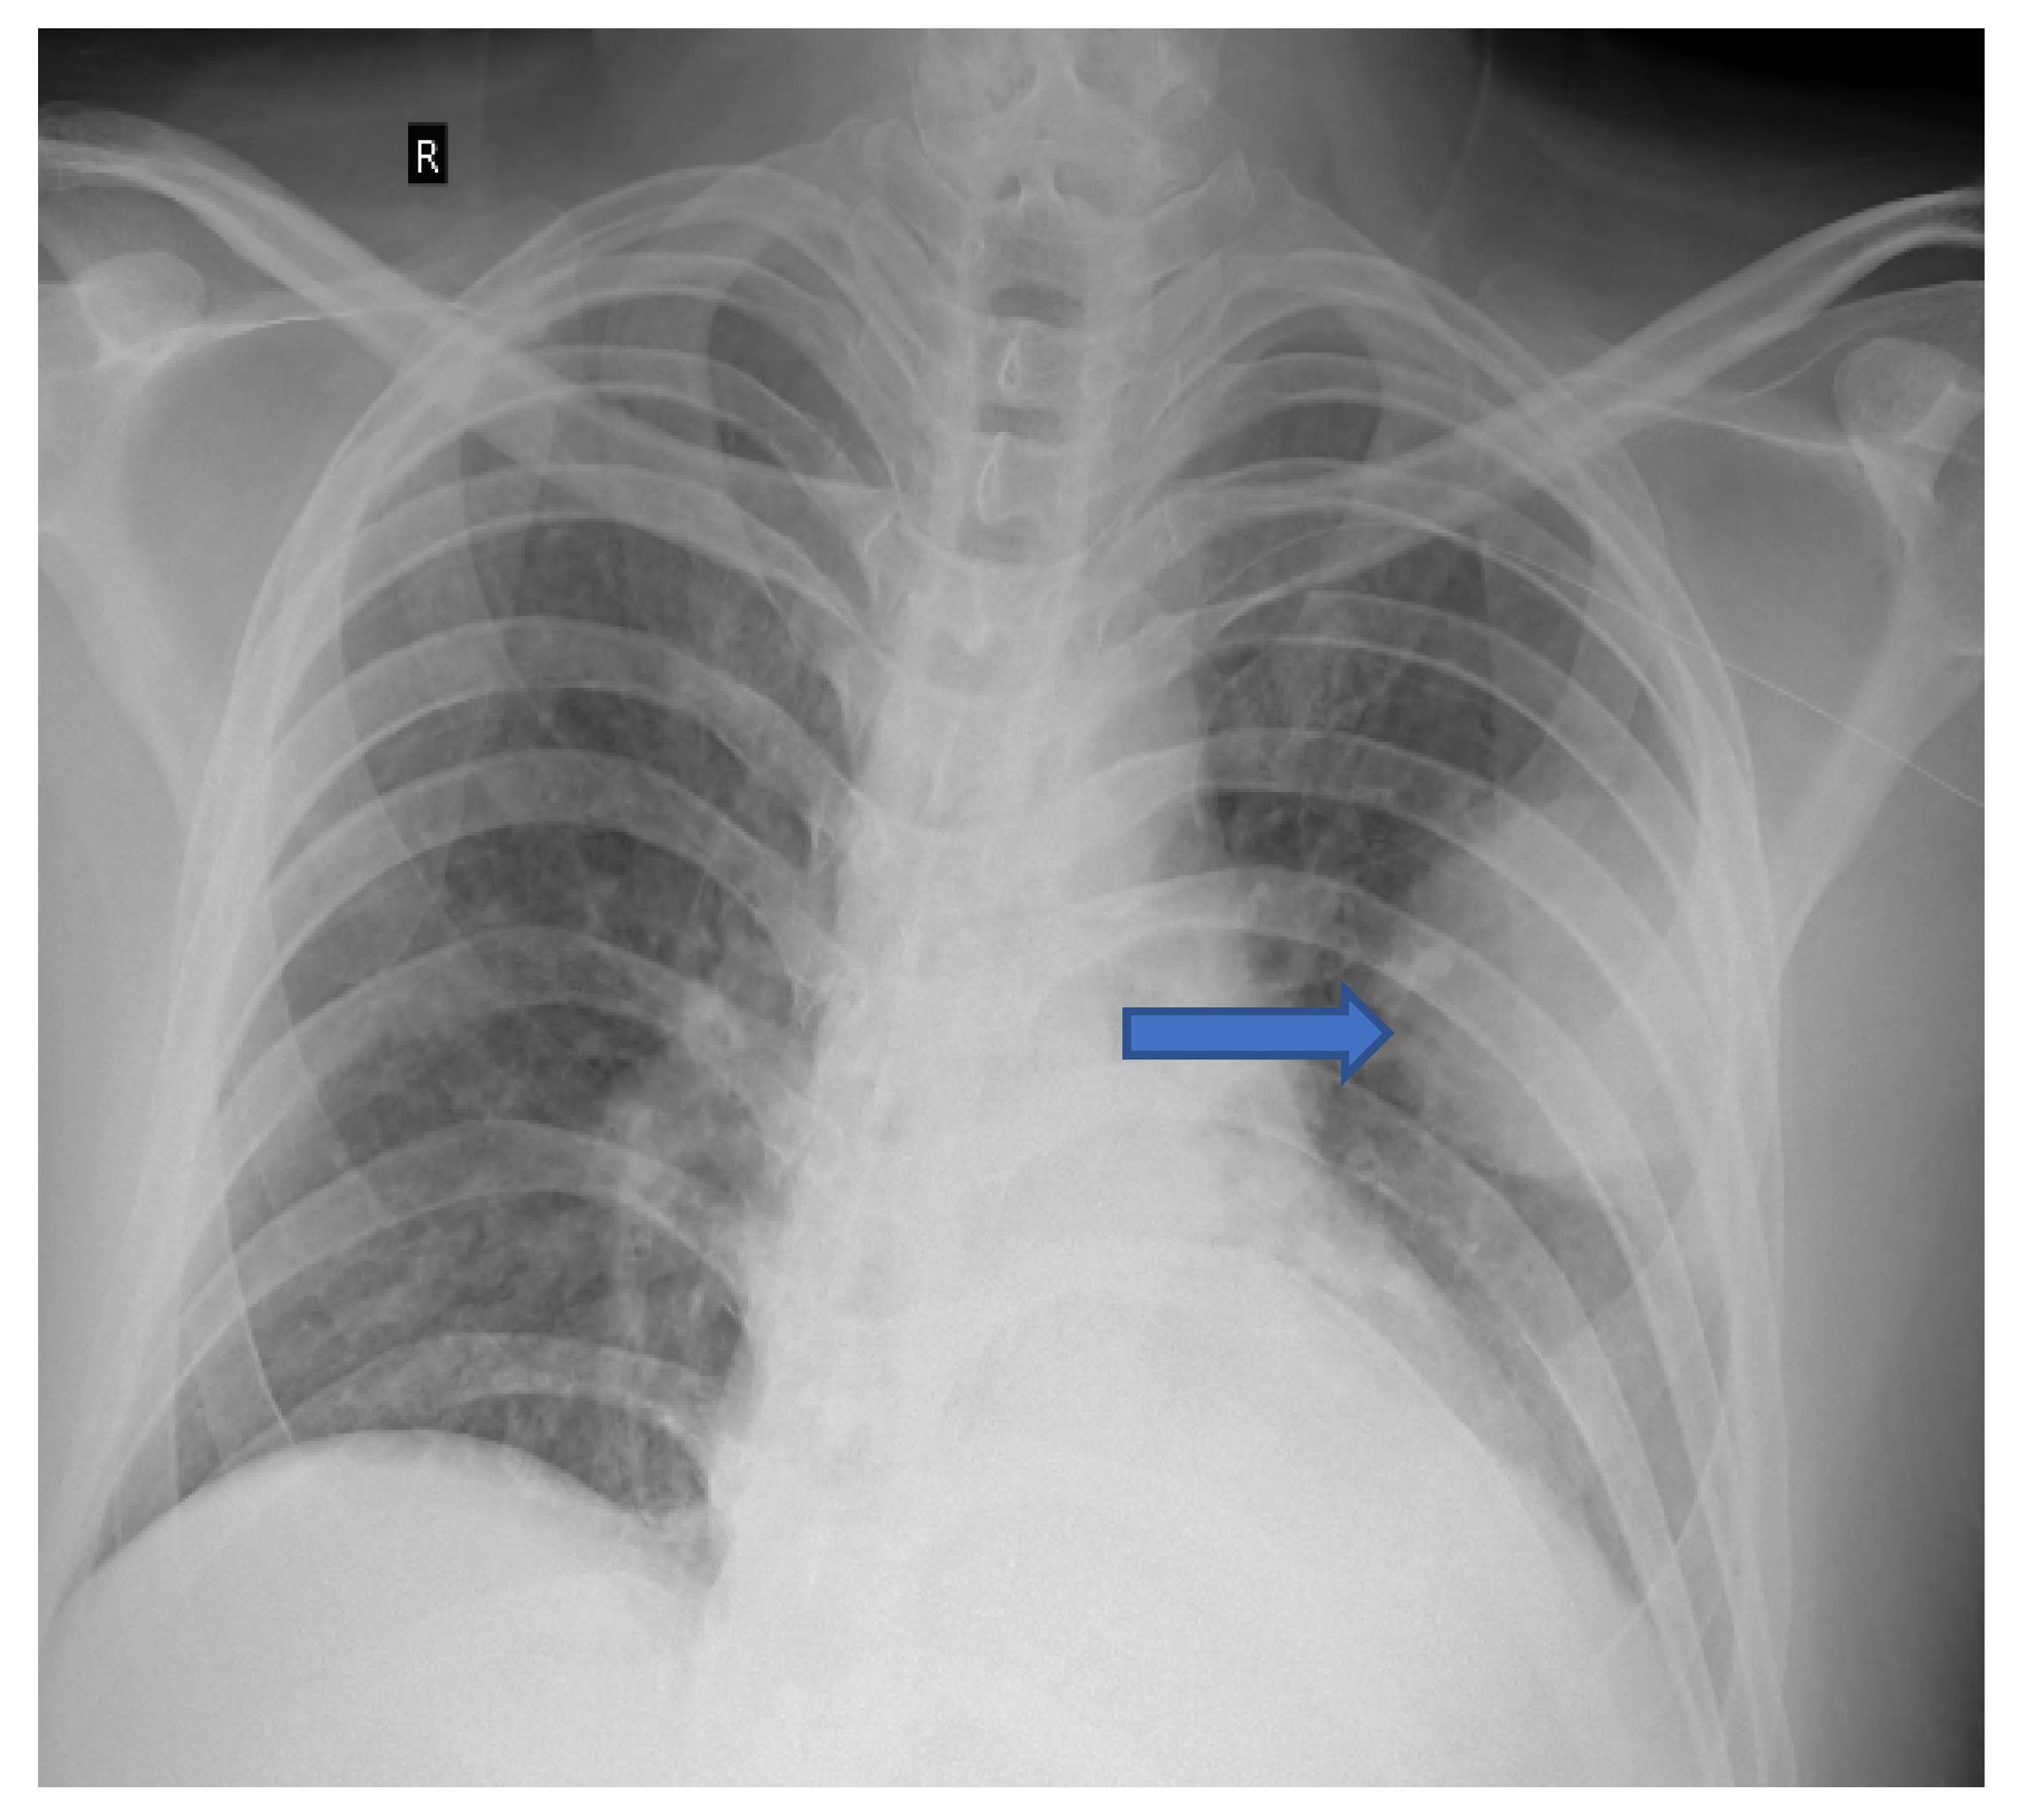

5.1. Role of Diagnostic Imaging

Diagnostic imaging is vital for early detection of invasive mucormycosis in patients with clinical suspicion. Certain distinguishing features of the lung parenchyma on a CT scan of the chest in patients with PM include multiple pulmonary nodules, often pleural-based, presence of lung cavitations and effusions (Figure 1, Figure 2, Figure 3 and Figure 4) [23]. The ‘reverse halo sign’ (central ground glass opacity surrounded by dense consolidation) is highly appreciated, mainly in neutropenic leukemic hosts. In a recent systematic review of CT findings in 16 patients with proven CAPM, consolidation and cavitation were seen in 11 (69%) patients, pleural effusion in 7 (47%), pneumothorax and nodules in 3 (19%) and ‘reverse halo sign’ and pulmonary embolism was seen in 2 (13%) patients [24]. Previously, Nam et al. reported that in hematologic patients, while consolidation and nodules are seen earlier in the disease process, central necrosis, cavitation and the air crescent sign are late findings [25]. This would suggest that CAPM is either under-diagnosed due to lack of differentiation from other fungal, including aspergillosis or bacterial pneumonias, or is diagnosed much later in the illness.

Figure 3. Multiple small nodules (blue arrows). Few show ‘tree in bud pattern’ in left lung parenchyma.